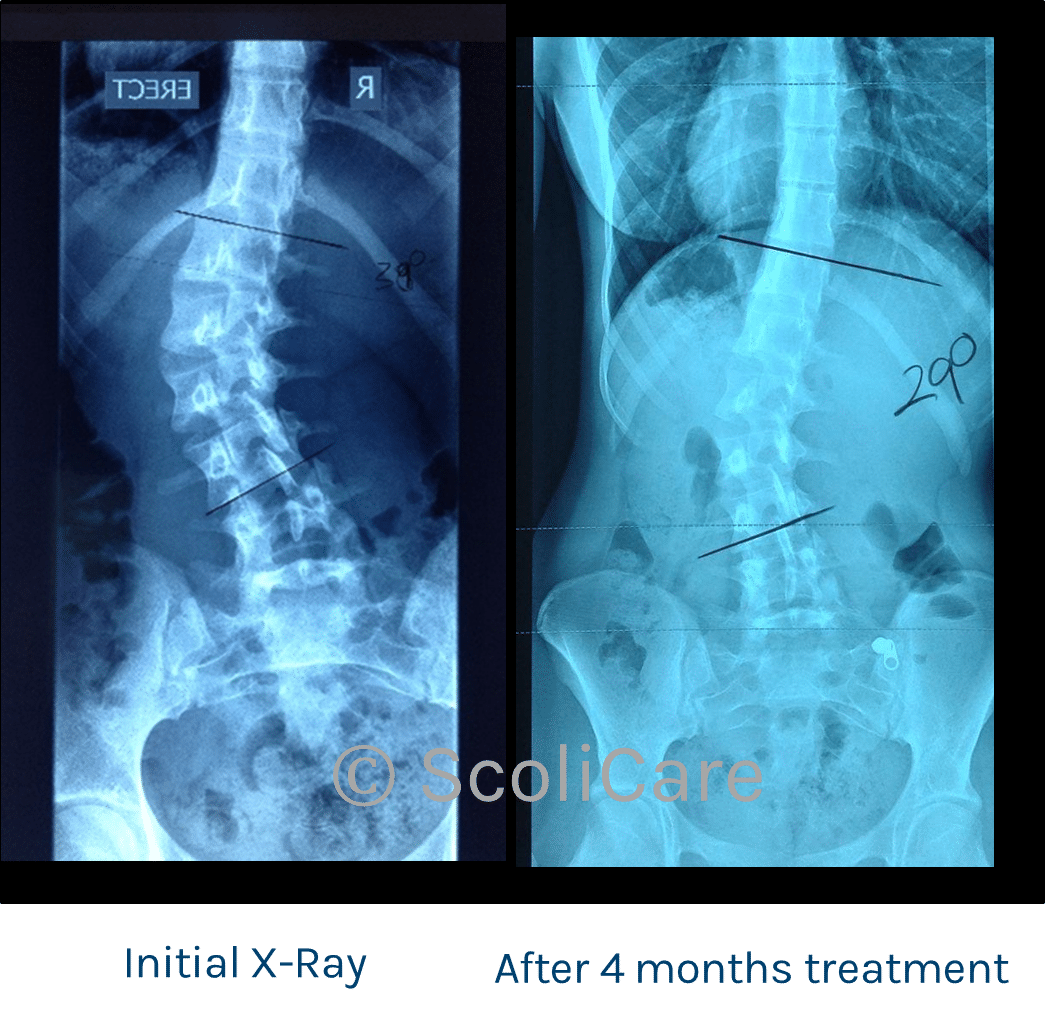

Female patient aged 18 years of age with a primary left thoracolumbar curve measured at 39 degrees (Cobb angle) and a right thoracic compensatory curve.

She was diagnosed with a left thoracolumbar curve measured at 39 degrees with a right thoracic compensatory curve.

After 4 months of treatment, an X-ray was taken and the curve had reduced from the initial 39 degrees to 29 degrees.